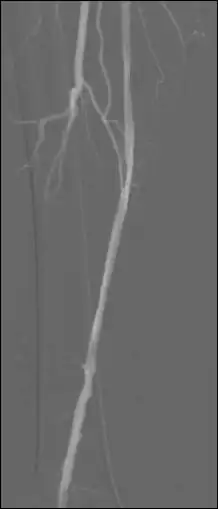

Use the up/down arrows to shift the relative position of the mask and live images in single pixel increments in both horizontal (X) and vertical (Y) dimensions, if needed.

Use the Thick Slab module, in the MinIP mode to (effectively) integrate a number of live images so as to generate a vascular trace.